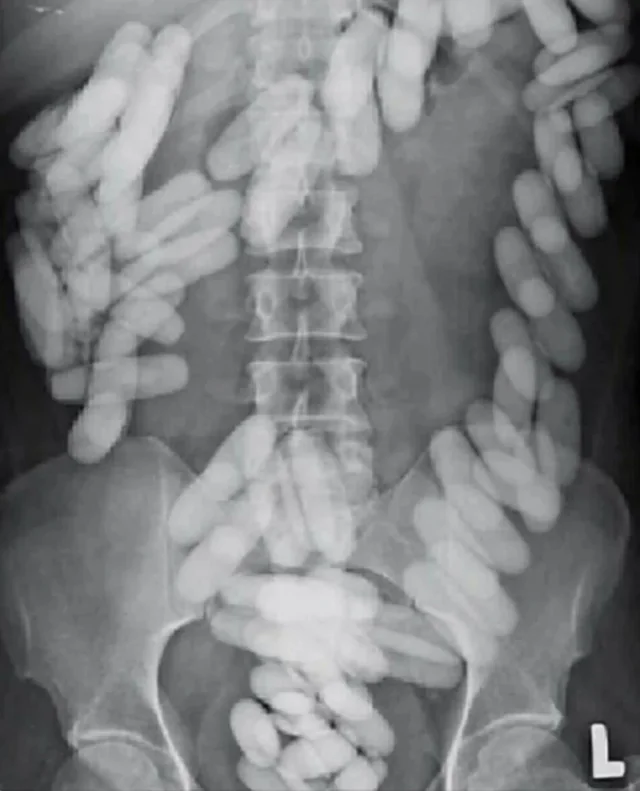

Sadly this is probably from a child who ate a bunch of magnets.

Is it not cocain smuggling via eating pods?

Maybe you’re right, but the hips look very small and the objects very uniform.

Lab stir bars are Teflon coated and look like candy. No idea where anyone could find that many stir bars.

do you know they’re stir bars? they look puffy and the magnet would be opaque…

Please tell me these are cocaine condoms and not actual stir bars like I thought when I first woke up and saw this

- those are huge stir bars